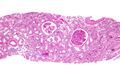

| Micrograph showing a glomerulus with changes characteristic of a transplant glomerulopathy. PAS stain. | |

Transplant glomerulopathy (TG) is a disease of the glomeruli in transplanted kidneys. It is a type of renal injury often associated with chronic antibody-mediated rejection. However, transplant glomerulopathy is not specific for chronic antibody-mediated rejection; it may be the result of a number of disease processes affecting the glomerular endothelium.[1]

It is characterized by glomerular basement membrane thickening (referred to as tram-tracking of the basement membrane), increased mesangial matrix and segmental and global glomerulosclerosis.[citation needed]